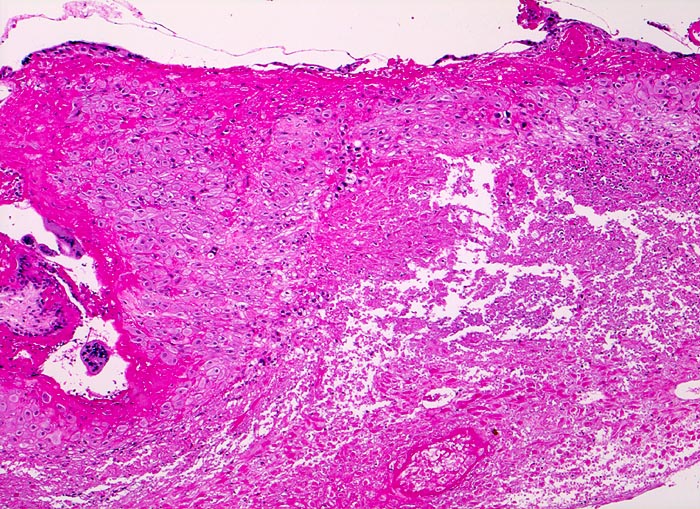

PathoPic ID 4676 - Abortkurettage: nekrotisches Deziudafragment

Abortkurettage: nekrotisches Deziudafragment

Nach längerer Retention zeigt die Dezidua eine ausgedehnte

granulozytär demarkierte Nekrose.

Synzytiotrophoblastäre Riesenzellen.

Missed abortion in der 11. Schwangerschaftswoche, sonographisch entsprechend der 9. Schwangerschaftswoche.

Ausgedehnte Nekrosen der Dezidua geben einen Hinweis auf ein länger zurückliegendes Abortgeschehen.

Vergrösserung

50